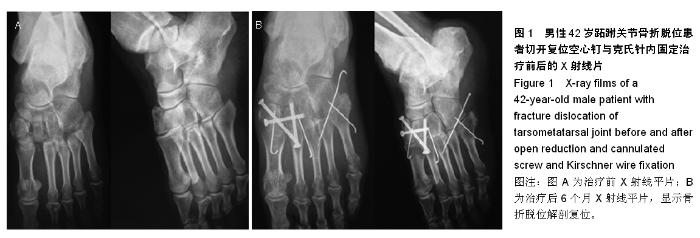

[24] 祝继明,郭亮.空心钉结合克氏针治疗跖跗关节骨折脱位[J].中国中西医结合外科杂志,2014,20(1):74-75.